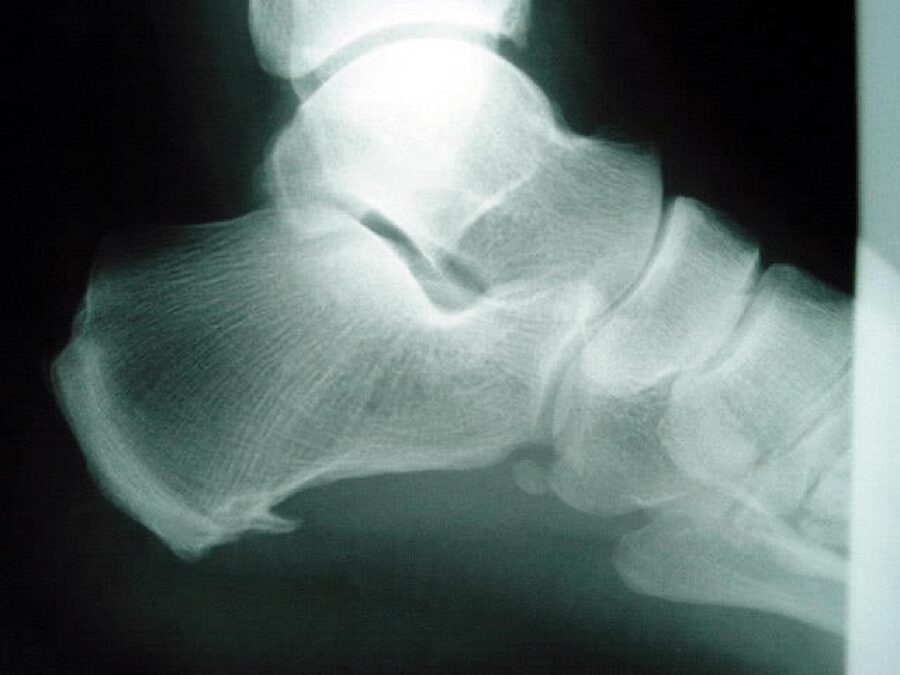

Il n’y a pas vraiment “d’épine” ! Ce qu’on observe à la radiographie est une calcification de l’enthèse du fascia plantaire c’est-à-dire là où il s’accroche sur le talon. Il y a un sur-tension : oui ! Mais c’est l’épine qui fait mal : non.

C’est les tissus autour de l’épine qui sont à l’origine des douleurs. En réduisant les tensions sur la chaine postérieure, les symptômes disparaîtront.